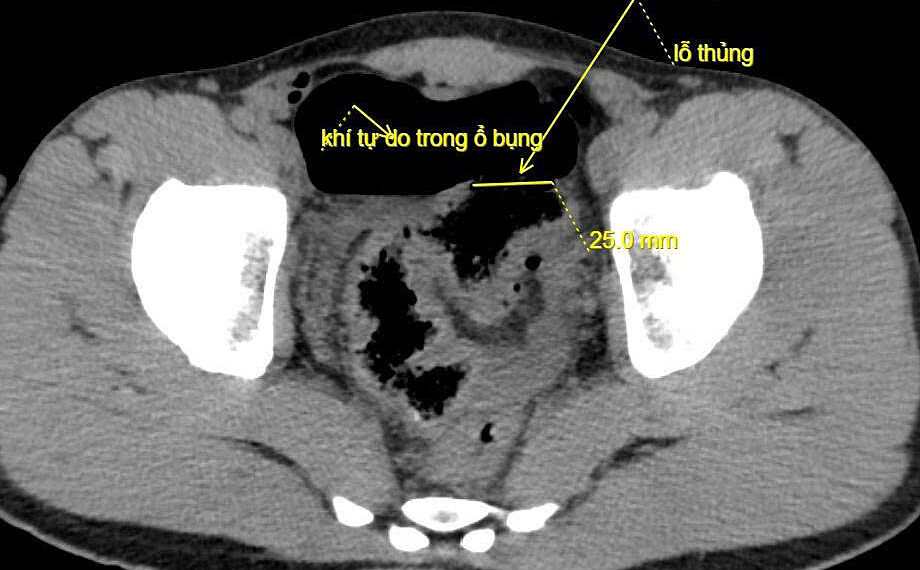

Ngày 20/10, đại diện Bệnh viện Đa khoa Lạng Sơn cho biết bệnh nhân đau bụng dữ dội, bụng chướng căng, khó thở và mệt lả. Kết quả chụp X-quang và CT thấy nhiều khí tự do trong ổ bụng bệnh nhân, bác sĩ nghi ngờ thủng tạng rỗng, chỉ định mổ cấp cứu.

Ảnh chụp CT ghi nhận đại tràng của bệnh nhân bị thủng. Ảnh: Bệnh viện cung cấp